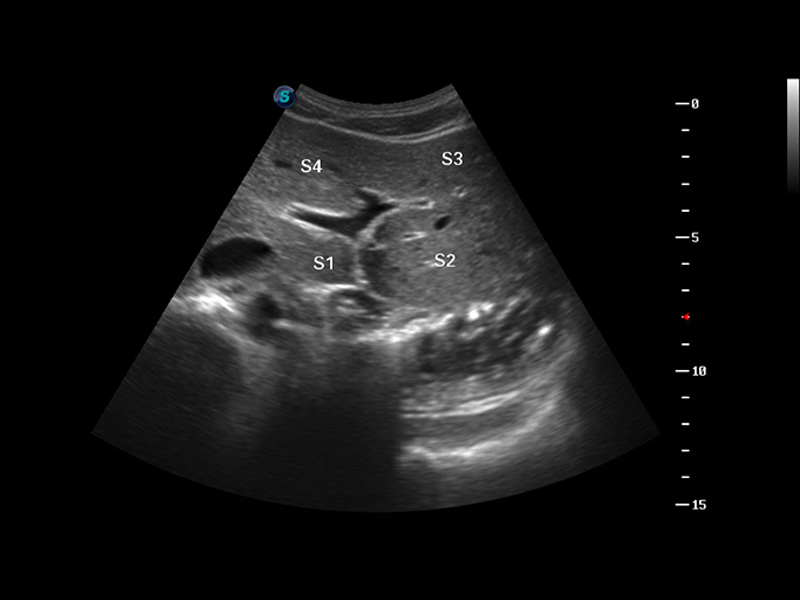

S8 EXP便携式彩色多普勒超声诊断仪是银河集团官网研发的高端全身应用型便携彩超。高通道的VIS平台融合可视化(Visual)、智能化(Intelligent)和人性化(Smart)的特点,配以银河集团官网自主研发生产的探头大家族,使您能够快速、准确的获得病人信息,提高工作效率的同时减轻疲劳。

成像技术

谐波成像

空间复合成像

3D/4D成像